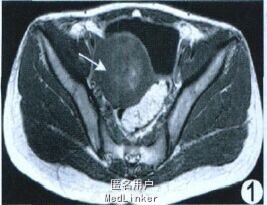

查体:子宫增大如孕8 周。实验室检查:血绒毛膜促性腺激素1.76 mIU/ml 。超声:子宫实性占位, 肌瘤变性。M RI :子宫明显不均匀增大, 宫腔内见约5.13 cm ×4.62 cm 类圆形异常信号, T1WI 呈等低信号, 其内见部分高信号(图1), T2WI 呈低信号, 其内夹杂线状、片状明显高信号(图2);增强后无强化(图3)。M RI 诊断为子宫腔内占位:子宫肌瘤(黏膜下型), 大部分变性。